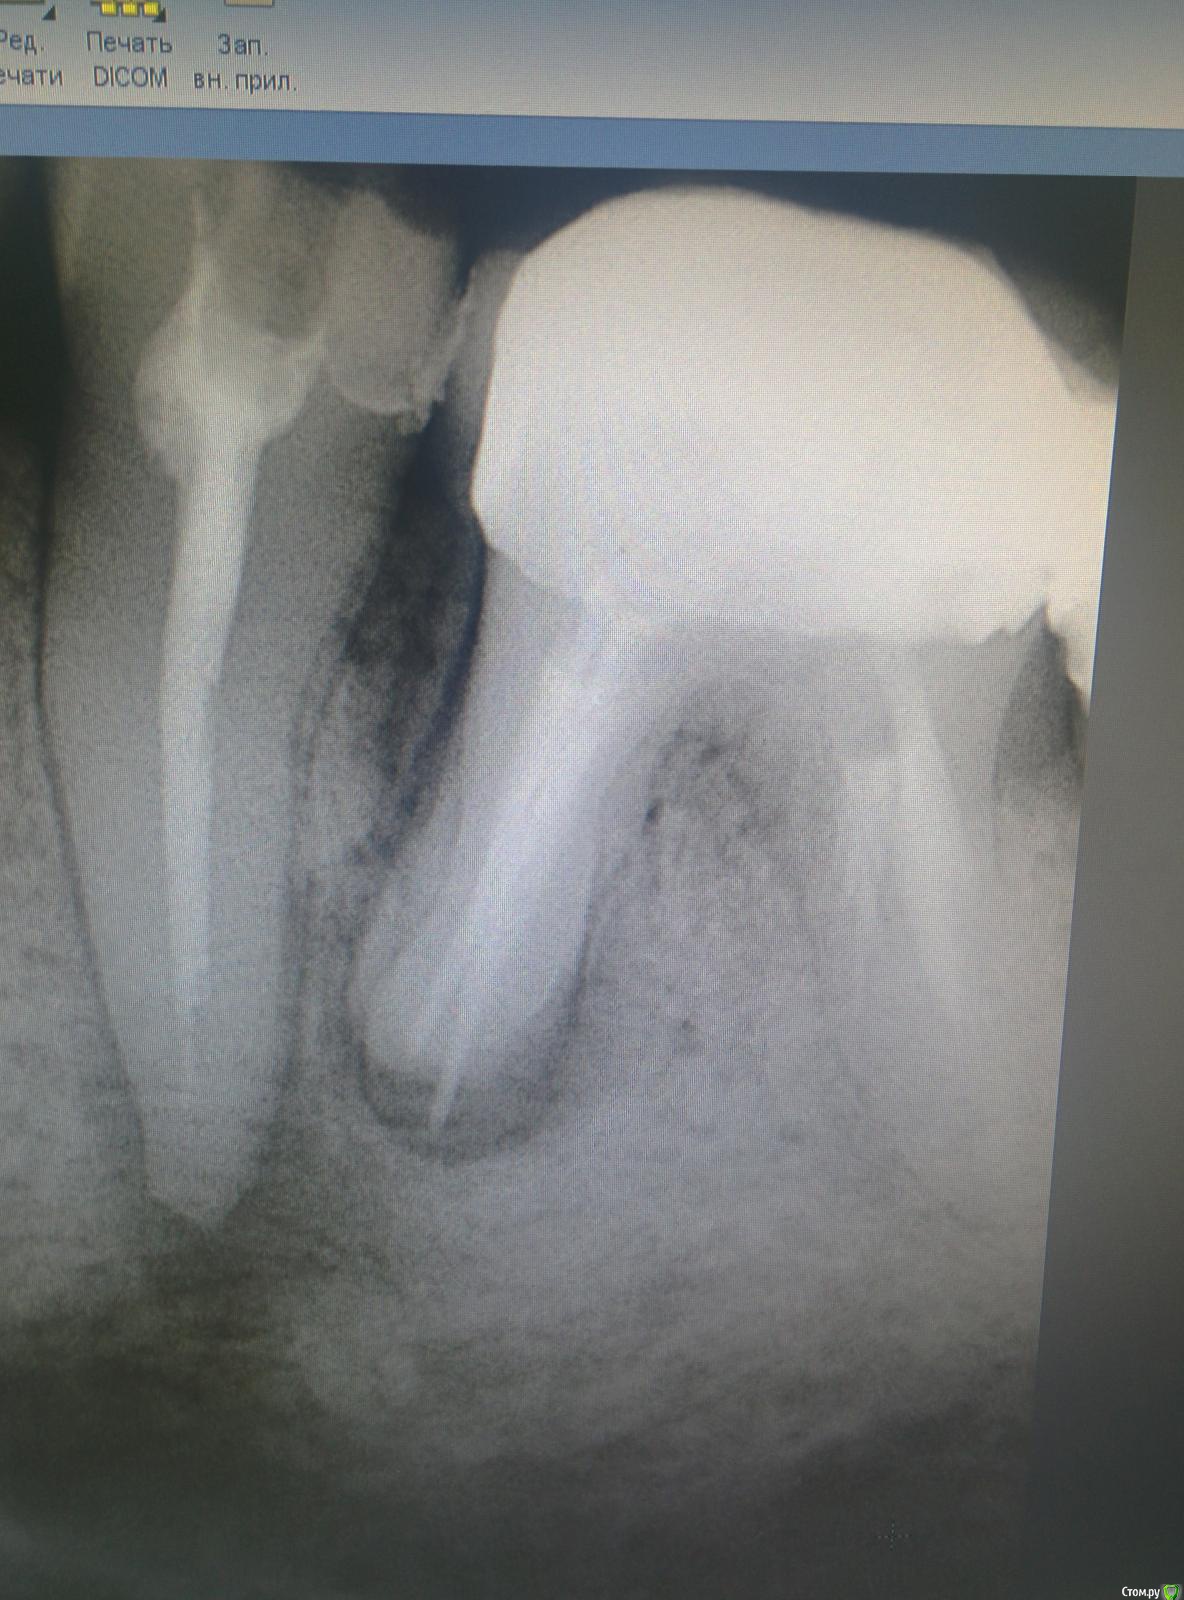

mermaid Опубликовано 18 февраля, 2015 Поделиться Опубликовано 18 февраля, 2015 Добрый вечер!ситуация следующая пол года назад в клинику пришла пациента с отеком на нижней челюсти слева.делаем снимоксразу думала 36,но перкуссия +только в 35,открыли,промыли(эдта+хлорка) ,Са,через 2 недели закрыла постоянно акросил+шрифты Через пол года рецидив,снова отек(36 лечить пациентка всячески отказывалась,уж очень не хотела снимать мостик)и снова перкуссия исключительно на 35 положительна,распломбировала,нашла подобие 2ого канала,долго мыла эдта,тёплой хлоркой,са.через 2 недели в день пломбировки снова отек....и опять мыла в коффере около часа,са.ещё через 2 недели пломбировка Поставили пломбочку...а через неделю звонок...снова отекли!!разобрали все-таки 36(резорцин более 20 лет,10 лет назад попытка перелечивания,костный карман..перфо в дистальном..хирург чешет лапки)Пациентка устала и готова к удалению(((где косяк???p.s.зондирование по по маргинальному краю в поисках трещины проводила,но провалов нетP.s.ещё смущает наличие плотного костного выбухания в области 35 Ссылка на комментарий

SDC Опубликовано 18 февраля, 2015 Поделиться Опубликовано 18 февраля, 2015 Про 36все понятно,перфо было старое,закрытое гуттой.Интересует лечение 35,что ещё предложите попробоватьНаблюдение. Если пообсуждать, то нужно пару прицельных снимков в боковых проекциях Ссылка на комментарий